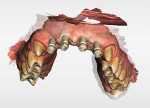

The implant/scan body manufacturer virtually designed the abutments and communicated with the clinician for approval of the virtual design (Figure 14). The abutments were then milled from titanium and gold coated and returned to the clinician. Once the custom abutments were designed and approved the practitioner obtained a core file from the manufacturer. This file can be exported back into the intraoral scanner (Primescan) or other CAD/CAM system for the design and manufacture of the temporary or permanent restorations. This core file is a virtual model with the custom abutments virtually seated as designed. In this case, the clinician 3D-printed (Primeprint, Dentsply Sirona) a Geller model to aid in adjusting and finishing the provisional restorations to help further develop the tissue prior to creation of the permanent restorations (Figure 15). A Geller model incorporates spaces to receive an individual die at each unit planned for fixed prosthetic units on the arch. The model, which was printed using model resin, was fabricated to have removable individual dies for each abutment (Nos. 7 through 10) and planned crown on the natural canines (Nos. 6 and 11) to aid in the fabrication of the planned provisional ceramic crowns (Figure 16).

Before receiving the custom abutments, the clinician used the core file sent from Atlantis (Figure 17, A and B) to design virtual crowns for each of the six anterior teeth (Figure 17, C). The core file gets imported back into the chairside software of the intraoral scanner (Primescan). Once the six crowns were designed, they were sent to the mill (Primemill) for milling of each individual crown (Figure 17, D). The crowns were milled from IPS e.max® CAD LT blocks (Ivoclar) in shade A2 on the Primemill, then glazed in a sintering oven (CEREC® SpeedFire, Dentsply Sirona). Final adjustments were made and finished on the previously printed Geller model (Figure 18).